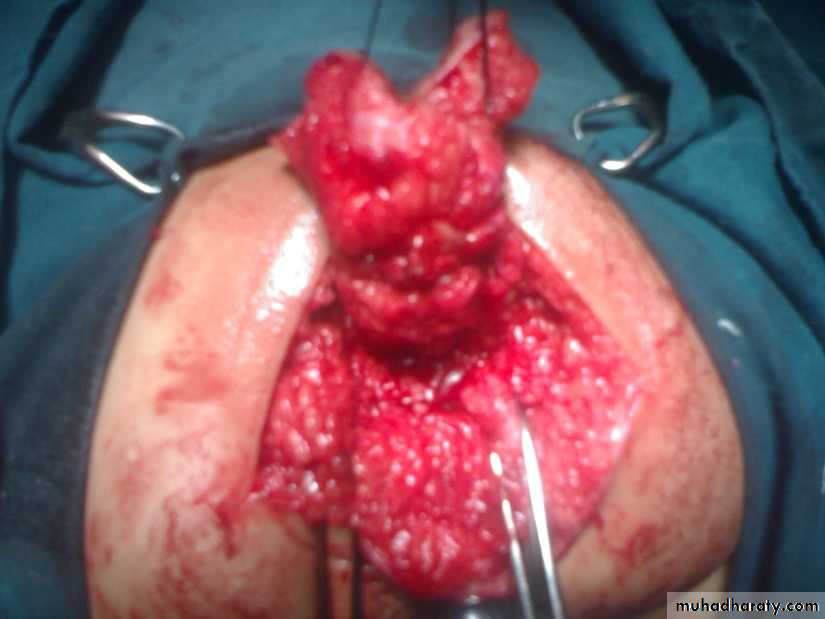

Sacrococcygeal teratoma